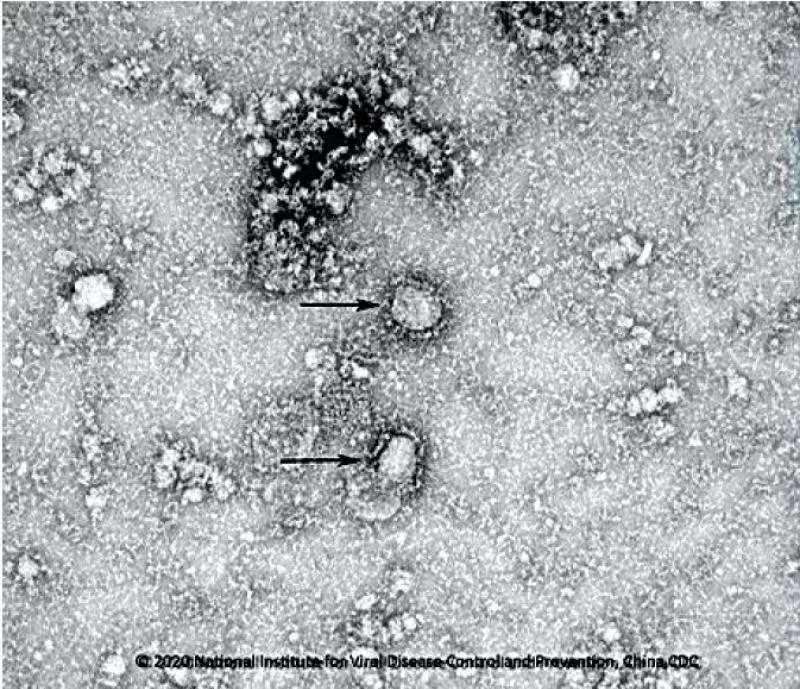

نشر العلماء الصينيون صوراً لفيروس كورونا الجديد التقطوها بواسطة مجهر إلكتروني.

وكشف معهد علم الأحياء الدقيقة التابع للأكاديمية الصينية للعلوم عن الصور في إطار حملة الوقاية والرقابة على تفشي الفيروس. وقامت وسائل الإعلام العالمية وغالبية شبكات التواصل الاجتماعي بإعادة نشر تلك الصورة.